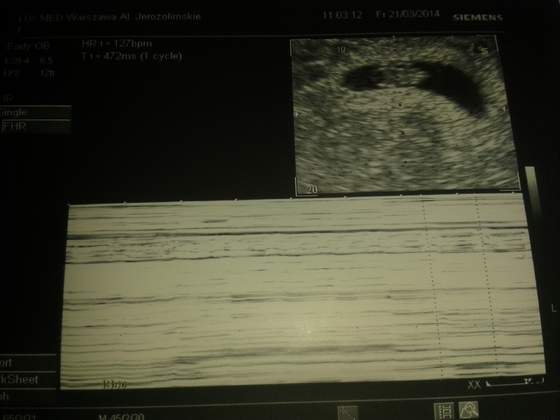

wizyta z usg dopiero 7.04...